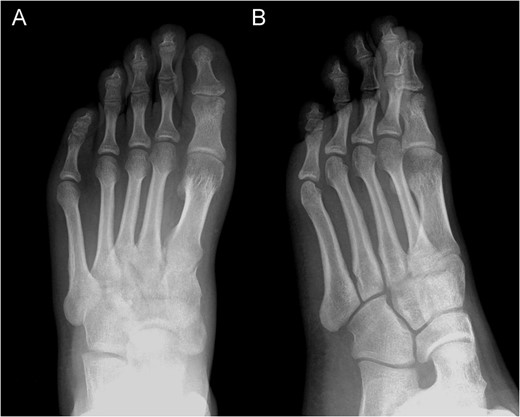

Posterior–anterior (A) and oblique (B) X-ray imaging of the left forefoot, showing the integration of the bone graft after 6 weeks.

Posterior–anterior (A) and lateral (B) X-ray imaging of the left foot, showing the arthrodesis without signs of recurrence after a follow-up of 30 months.